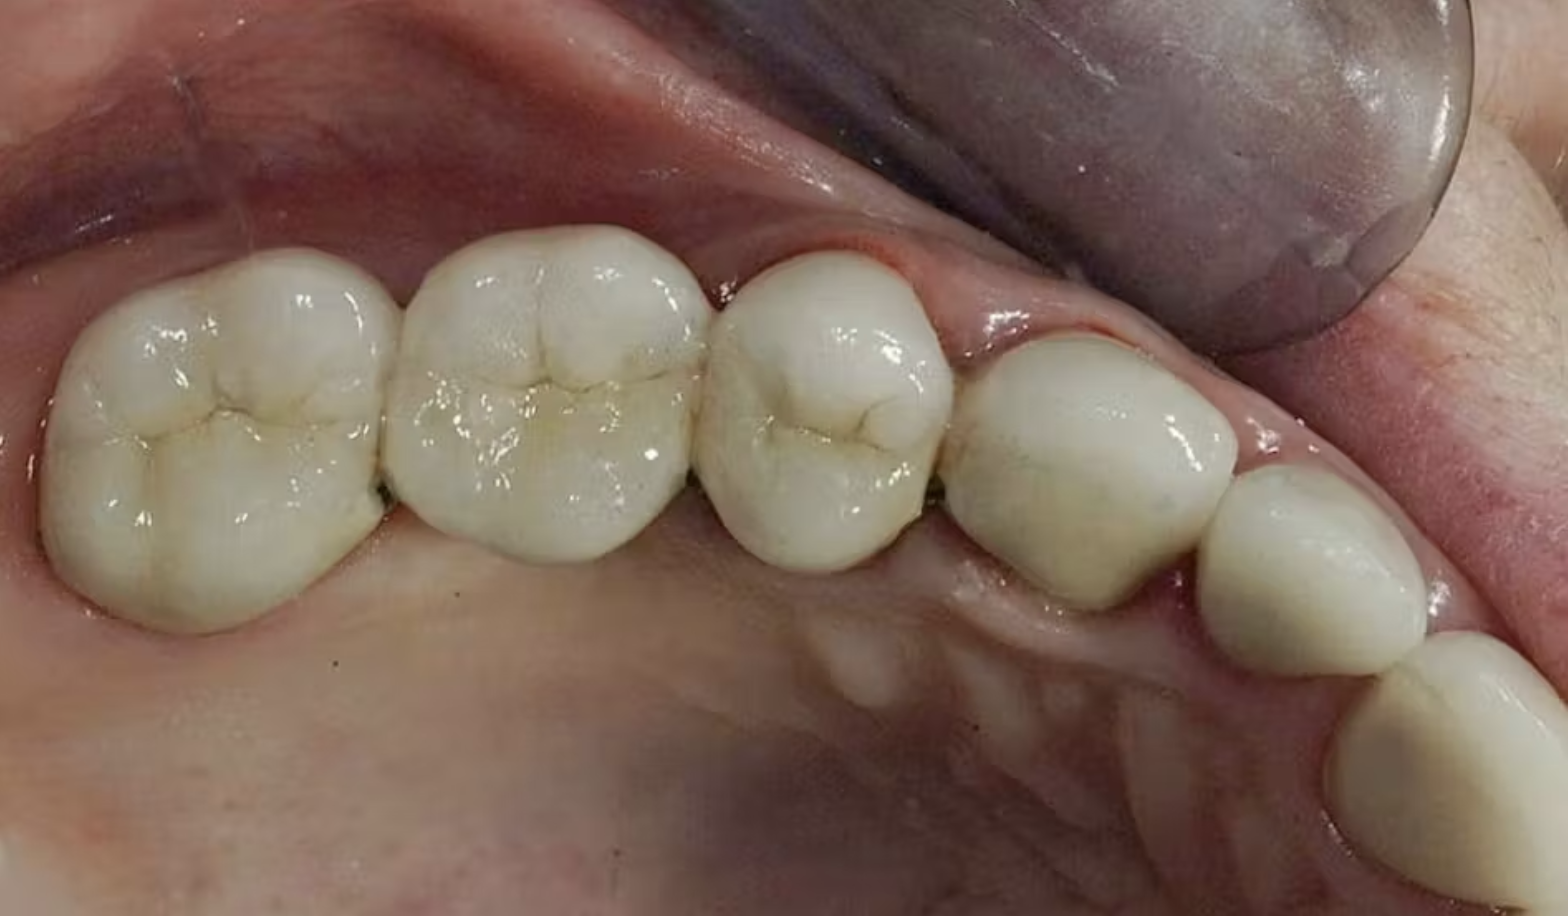

Hình 2:

Tái tạo cùi răng

Hình 3: Gắn phục hình cầu răng sứ